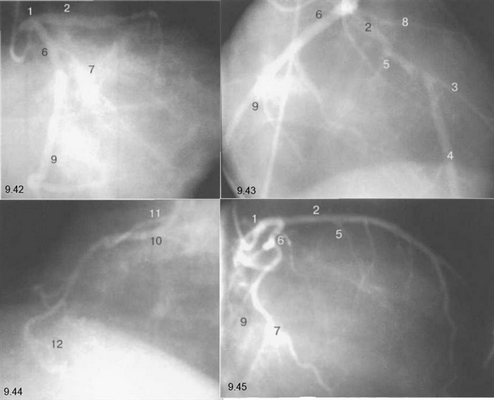

На следующих рисунках представлены два типа коронарного кровообращения — правый и левый и характеризующиеся неравномерным развитием правой коронарной и огибающей (ветвь левой коронарной артерии) артерий. При левом типе отмечается выраженная периферия огибающей артерии при значительной гипоплазии правой коронарной артерии. При правом типе чаще всего хорошо развита маргинальная ветвь и гипоплазирована основная ветвь огибающей артерии. Периферия правой коронарной и, в особенности, правая левожелудочковая ветвь значительно выражены и превосходят огибающую по размерам зоны кровоснабжения.

Рис. 9.42-9.44 — левый тип коронарного кровообращения.

Рис. 9.45 и 9.46 — правый тип коронарного кровообращения.

Рис. 9.42. Левая коронарная артерия. Правая косая проекция.

Рис. 9.43. Левая коронарная артерия. Проекция «паук».

Рис. 9.44. Правая коронарная артерия. Левая косая проекция.

Рис. 9.45. Левая коронарная артерия в правой косой проекции.

Рис. 9.46. Правая коронарная артерия в переднезадней проекции.